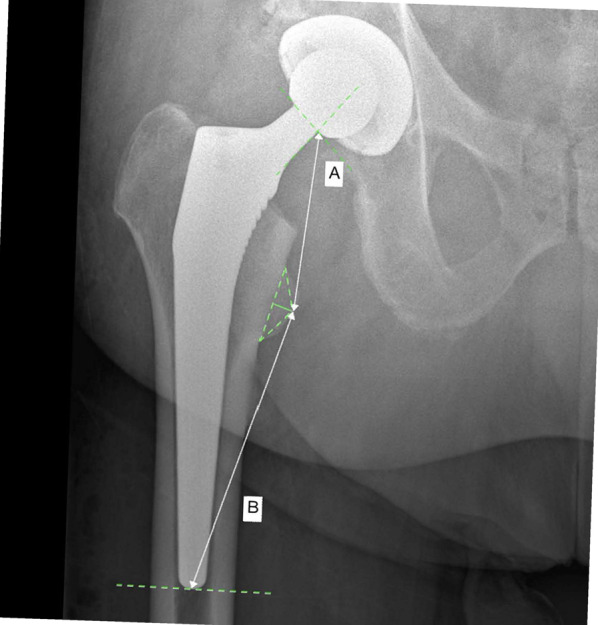

Methods: The present study was conducted following the STROBE guidelines. The records of patients who underwent THA between 2016 and 2023 were accessed. All patients who underwent two-staged bilateral THA were retrieved. The direct contact between the stem and the cortical bone was assessed at various points in the metaphysis and the distal portion of the stem (diaphysis) in both anteroposterior radiographs of the pelvis (medial and lateral bone contact) and a Lauenstein view of the hip (anterior and posterior bone contact). The following parameters were measured and compared to assess stem subsidence: distance from the proximal femur at the stem bone interface and the tip of the lesser trochanter (distance A); distance from the tip of the lesser trochanter and the tip of the femoral stem (distance B).

Results: In total, 250 patients were included, 45% (149 of 250 patients) were women and 61% (153 of 250 THAs) were implanted primarily on the right side. The mean age of patients at the time of the first THA was 64.3 ± 10.0 years and the mean body mass index (BMI) was 28.0 ± 4.9 kg/m2. The mean length of the follow-up was 14.1 ± 10.8 months. The overall stem subsidence following THA was 2.8 ± 0.7 mm (P < 0.006). A direct cortical bone-implant contact did not exert a statistically significant difference in subsidence of the THA stem at the metaphysis and diaphysis (P > 0.5). Stem subsidence following THA with a collarless cementless Corail stem was approximately 2.8 mm at 14 months.